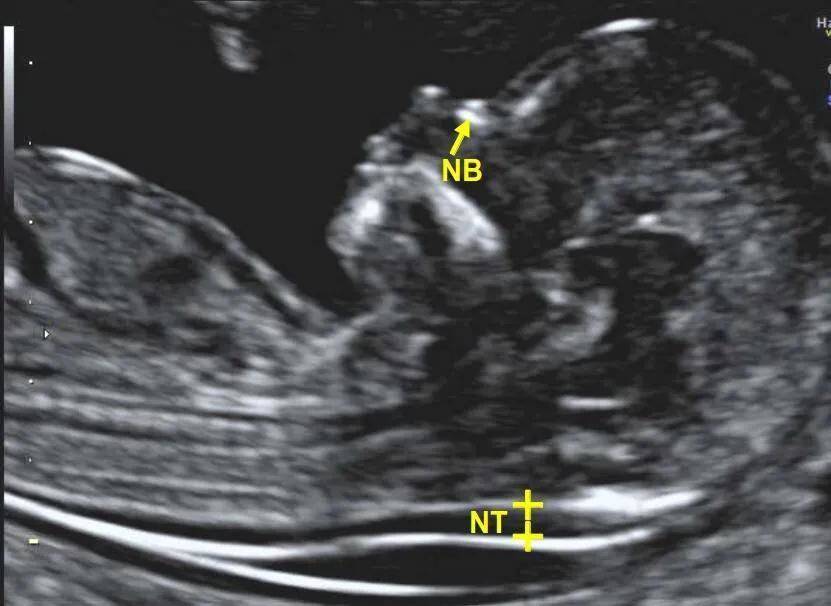

NT的中文名称叫做“胎儿颈项部透明层厚度”,也就是胎儿颈背部的皮肤和筋膜之间的带状软组织厚度。简单点理解就是胎儿在特定时间通过B超标准切面测量的颈部一层软组织的厚度。

很多孕妇很烦恼,就是检查的时候经常被告知已经超过了NT的检查孕周。那么,为什么这个检查这么苛刻,一定要挑11-13周+6这个时间范围呢?这就和NT的形成有关系了,颈项透明层其实就是在胚胎淋巴系统未完善之前,积聚在颈部淋巴囊(管)中的淋巴液。到了14周以后,随着淋巴系统逐渐发育完善,这些淋巴液就会慢慢被引流消失了。所以错过了这个时间段就失去了检查NT的时机。

不能错过就意味着它非常重要,因为一旦发现NT超标,就提示胎儿畸形的风险在增加,而且超标越多,风险就越大。目前,大部分医院的NT标准都是小于2.5mm,如果检查发现NT大于等于2.5mm就意味着超标了。和NT增厚关联最密切的问题就是胎儿染色体的异常,主要是染色体非整倍体异常。大家都知道,人类有46条染色体,也就是23对,我们把它们标记为1-22号,另外再加一对性染色体。非整倍体就是某一号的染色体不是一对,而是三条,多出来一条。和NT增厚关系最密切的就是21三体(21号染色体有三条),此外18三体、13三体、15三体、X单体(性染色体只有一条X,少了一条),三倍体(全部都多一条)等。可想而知,染色体异常必然会导致很多畸形和其他严重后果。

除了和染色体异常有关,一些NT超标的胎儿虽然染色体数目是正常的,但存在严重的畸形和一些罕见的综合征,这些很多就属于基因层面的异常了。和NT超标关联最大的畸形就是先天性心脏病,此外呼吸、泌尿、消化、骨骼系统及神经系统的畸形都可能存在。所以说在早孕期筛查NT既能够再次核对孕周,又能够进行一次严重结构畸形的筛查(无脑儿、胸外心等),可以理解为一次小排畸。最重要的是通过测量NT的厚度,来评估出染色体异常或者严重畸形的风险,敲响警钟,便于及早进行进一步检查。